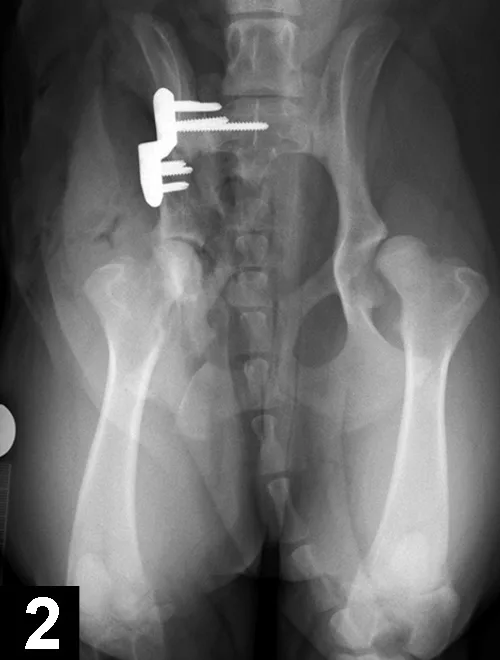

Figure 2. Postoperative ventrodorsal radiograph of the pelvis after triple pelvic osteotomy.

Case selection is important, as some factors (eg, age, subluxation and reduction angles, acetabular coverage of the femoral head) may affect the success of these procedures (eg, juvenile pubic symphysiodesis, triple pelvic osteotomy [TPO, Figure 2], double pelvic osteotomy [DPO]). Salvage procedures (eg, total hip replacement, femoral head and neck excision) are usually reserved for severe cases that do not respond to conservative treatment and are performed after growth has ceased.